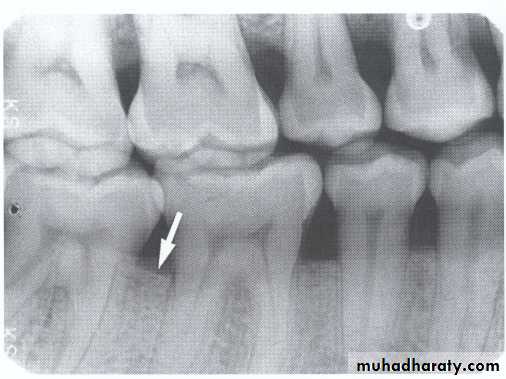

3.Furcation involvements:

Bone loss in the furcation area of the roots which is evidence of advanced disease in multirooted

teeth.

Initially seen as widening of the PL space at the crest of

the furcation . As lesion progresses, the bone

loss progresses apically.

Mild/moderate/sever.